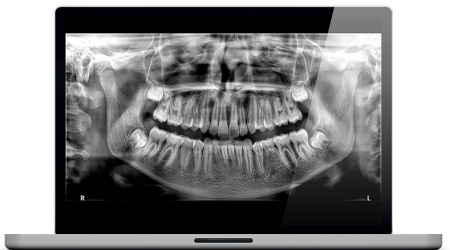

IMÁGENES PANORÁMICAS DEFINIDAS

Nuestro nuevo algoritmo Tomosharp se combina con el posicionamiento basado en IA para ofrecer imágenes panorámicas ultranítidas en cuestión de segundos.